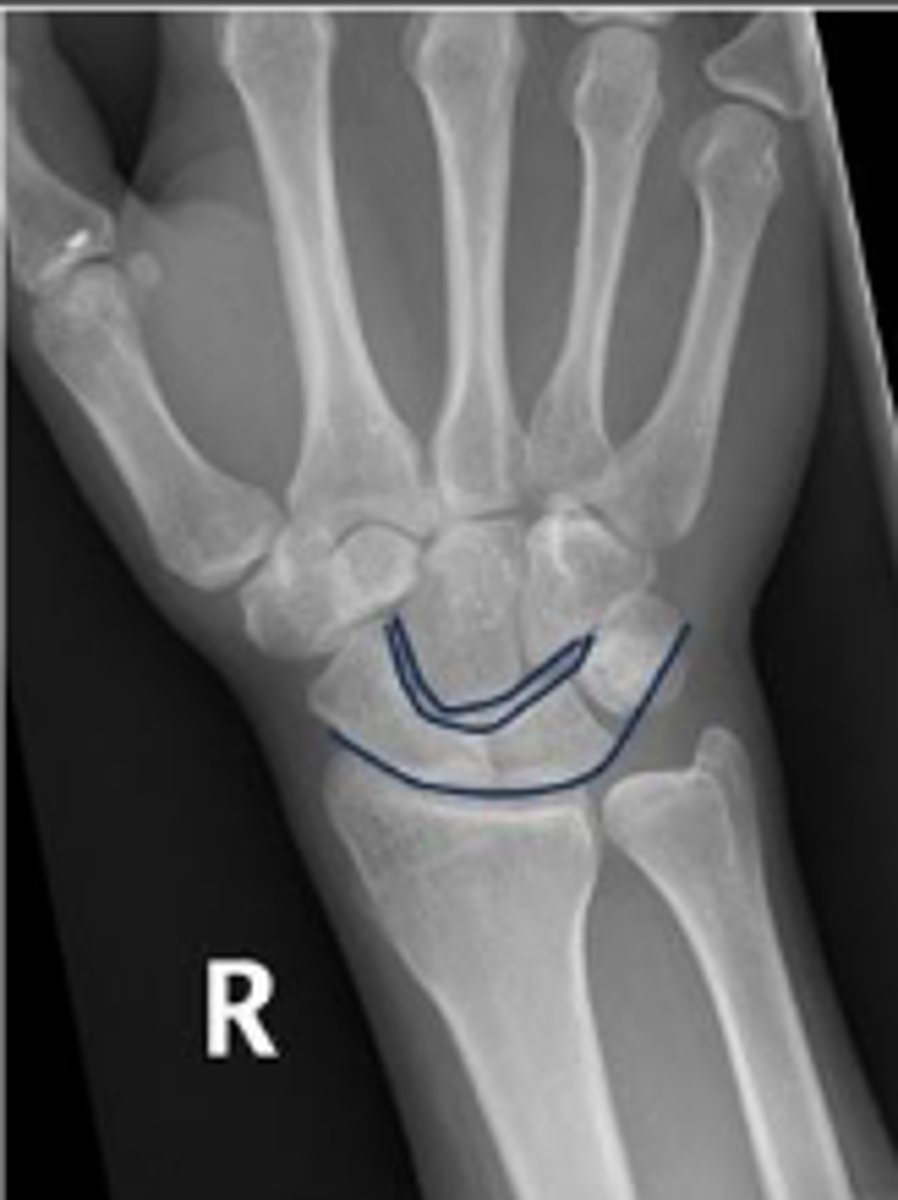

3 arcs of carpal alignment

What is the name of the assessment

Proximal cortical aspect of the first (proximal)

carpal row (ARC 1)

What are the landmarks for the most proximal line in the assessment?

Distal cortical aspect of the first (proximal) carpal

row (ARC 2)

What are the landmarks for the most middle line in the assessment?

Proximal cortical aspect of the second (distal)

carpal row (ARC 3)

What are the landmarks for the most distal line in the assessment?

SLAC wrist; carpal dislocation, carpal fracture

Name 2 conditions that will result in an alteration of the assessment?